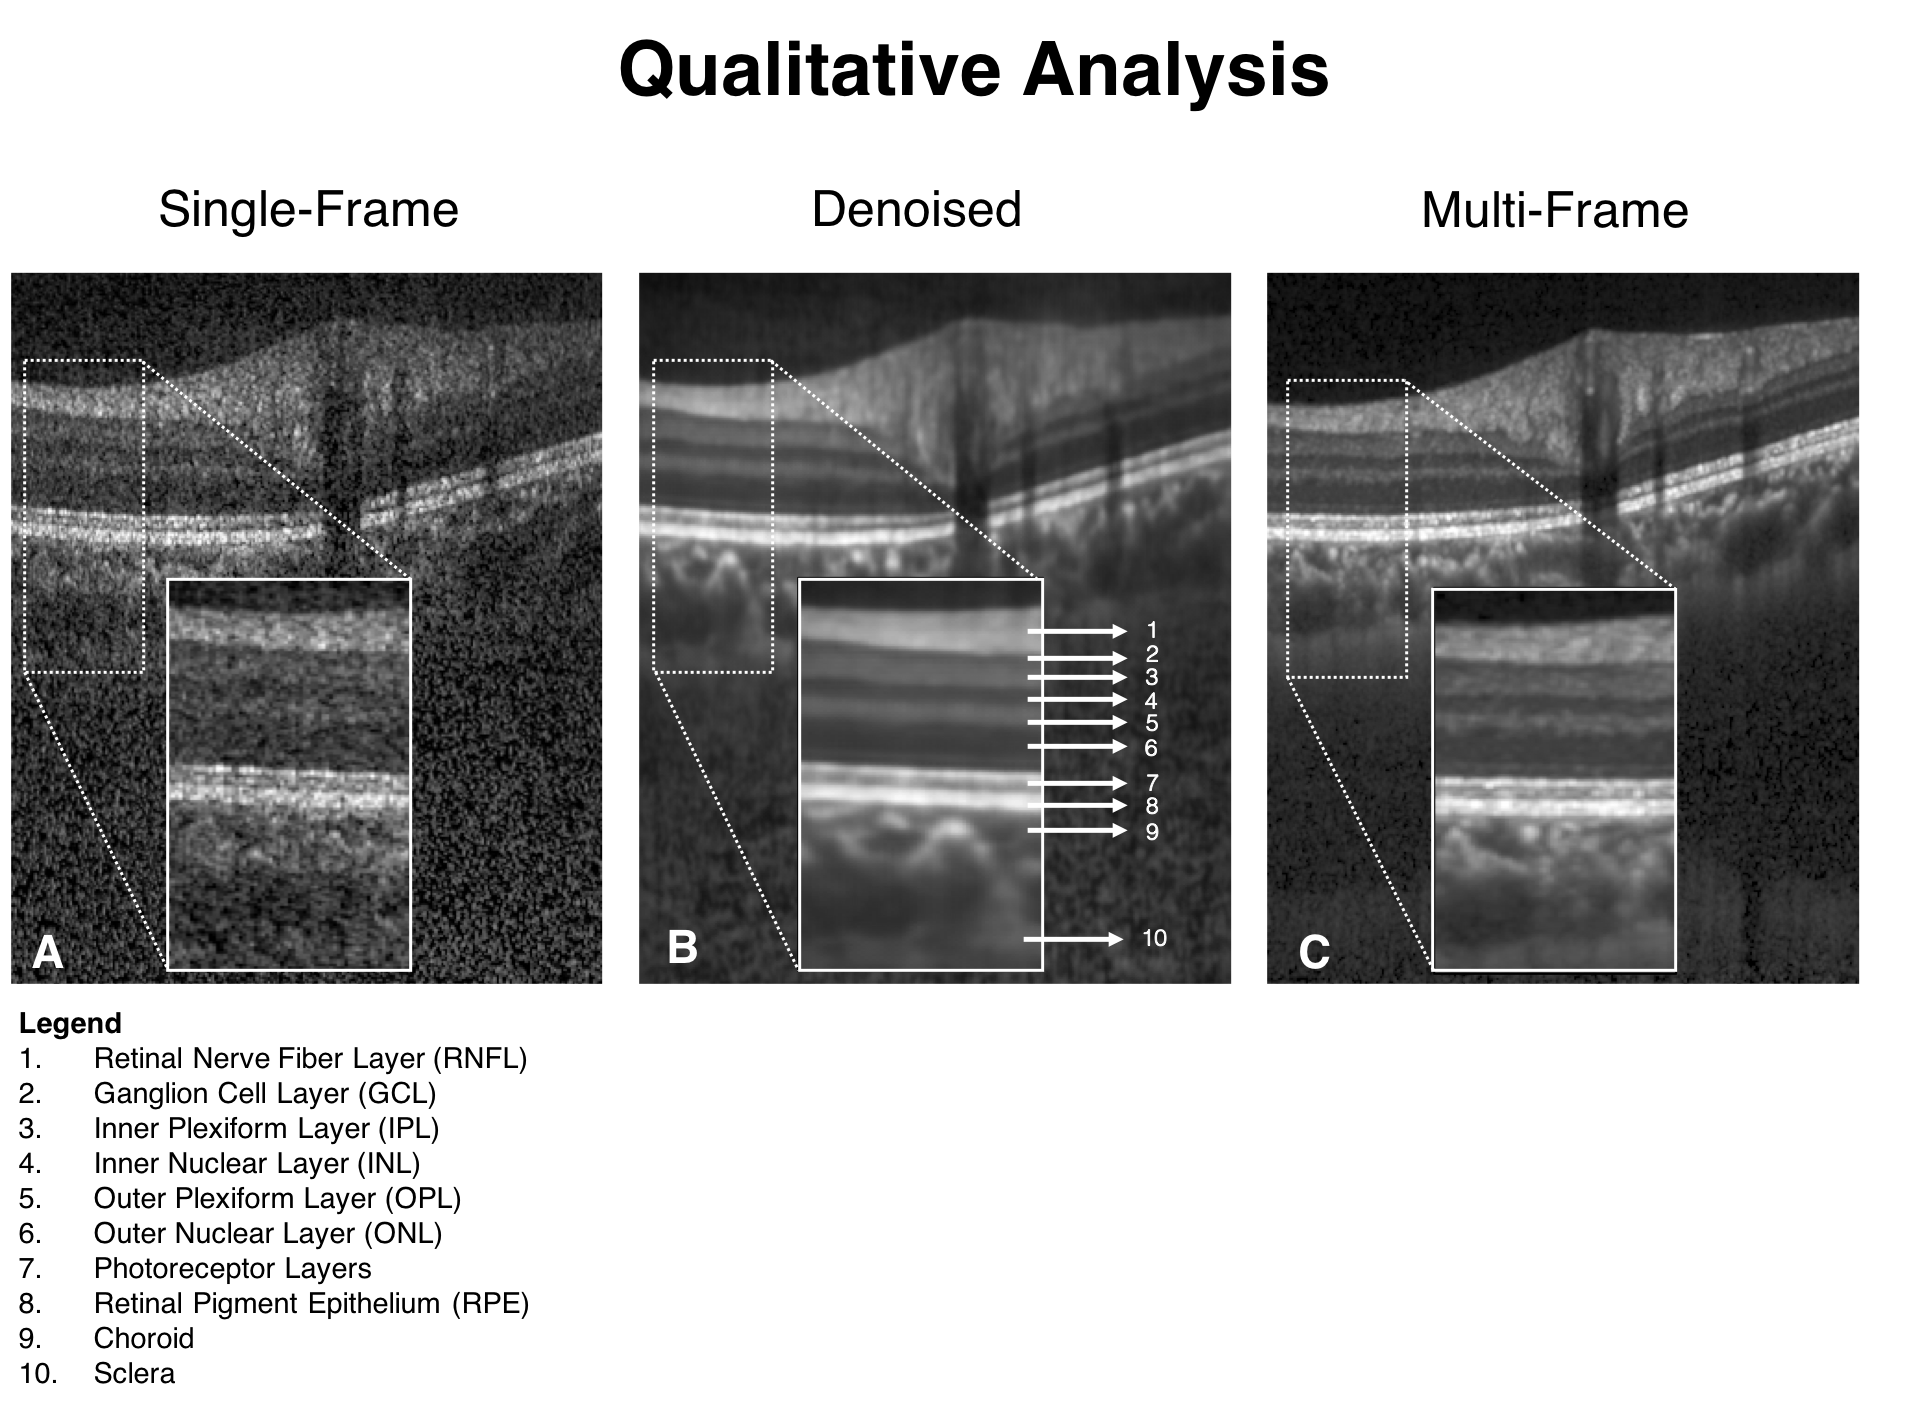

When trained with the ‘clean’ B-scans (multi-frame) and the corresponding ‘noisy’ B-scans, our network was able to successfully denoise unseen single-frame B-scans. The single-frame, denoised and multi-frame B-scan for a healthy subject can be found in (Figure 3). In all the cases, the denoised B-scans were qualitatively similar to their corresponding multi-frame B-scans (Figure 4). Overall, the visibility of all ONH tissues were prominently enhanced (Figure 3; B).

Using the proposed network, we obtained denoised B-scans that were qualitatively similar to their corresponding multi-frame B-scans (Figure 3) and (Figure 4), owing to the reduction in noise levels. The mean SNR for the denoised B-scans was dB, a two-fold improvement (reduction in noise level) from improvement from dB that was obtained for the single-frame B-scans, thus offering an enhanced visibility of the ONH tissues. Given the significance of the neural (retinal layers) [79, 80, 81, 82, 83] and connective tissues (sclera and LC) [84, 85, 86, 87, 88], in ocular pathologies such as glaucoma [2], and age-related macular degeneration [89], their enhanced visibility is critical in a clinical setting. Furthermore, reduced noise levels would likely increase the robustness of aligning/registration algorithms used to monitor structural changes over time [18]. This is crucial for the management of multiple ocular pathologies [90, 91].

In denoised B-scans (vs single-frame B-scans), we consistently observed higher contrast across tissues. Our approach enhanced the visibility of small (e.g. RPE and photoreceptors) and low-intensity tissues (e.g. GCL and IPL; Figure 3 B). For all tissues, the mean CNR increased from (single-frame) to (denoised). Since existing automated segmentation algorithms rely on high contrast, we believe that our approach could potentially reduce the likelihood of segmentation errors that are relatively common in commercial algorithms [15, 16, 17, 92]. For instance, the incorrect segmentation of the RNFL can lead to inaccurate thickness measurements, leading to under-/over- estimation of glaucoma [19]. By using the denoising framework as a precursor to automated segmentation/thickness measurement, we could increase the reliability [93] of such clinical tools.